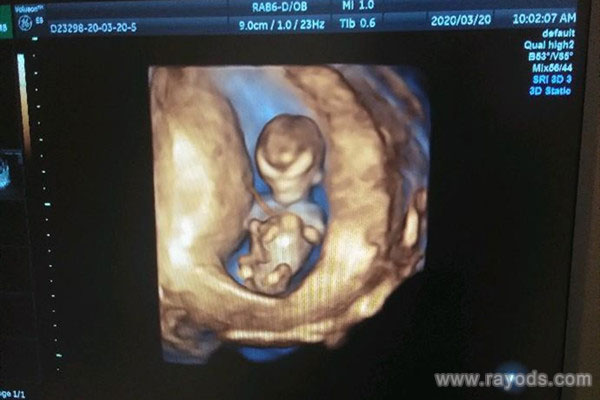

就NT头型看男女,网传的说法是看胎儿的额头大小,据说额头比较宽大、比较凸出的就是女孩,额头平平的就是男孩。还有的说看头骨,一般都是男孩头大身体小,女孩都是头小身体大,如果是这么判断的话,额头大小看男女就不成立,因此这个方法是没有任何科学依据的。

就根据这个头型看男女,网上有相关的帖子表明具体的分辨方法,就如NT图中宝宝头骨平滑或突出来分辨男女宝宝的准确率也是很高的呢!宝宝头骨平滑为男,突出为女。很多人都觉得这个方法要比nub点分辨男女更准确。其实不单单只是NT头型看男女,对于这个NT检查,网传还可以根据其他数据分辨,就如看NT值。